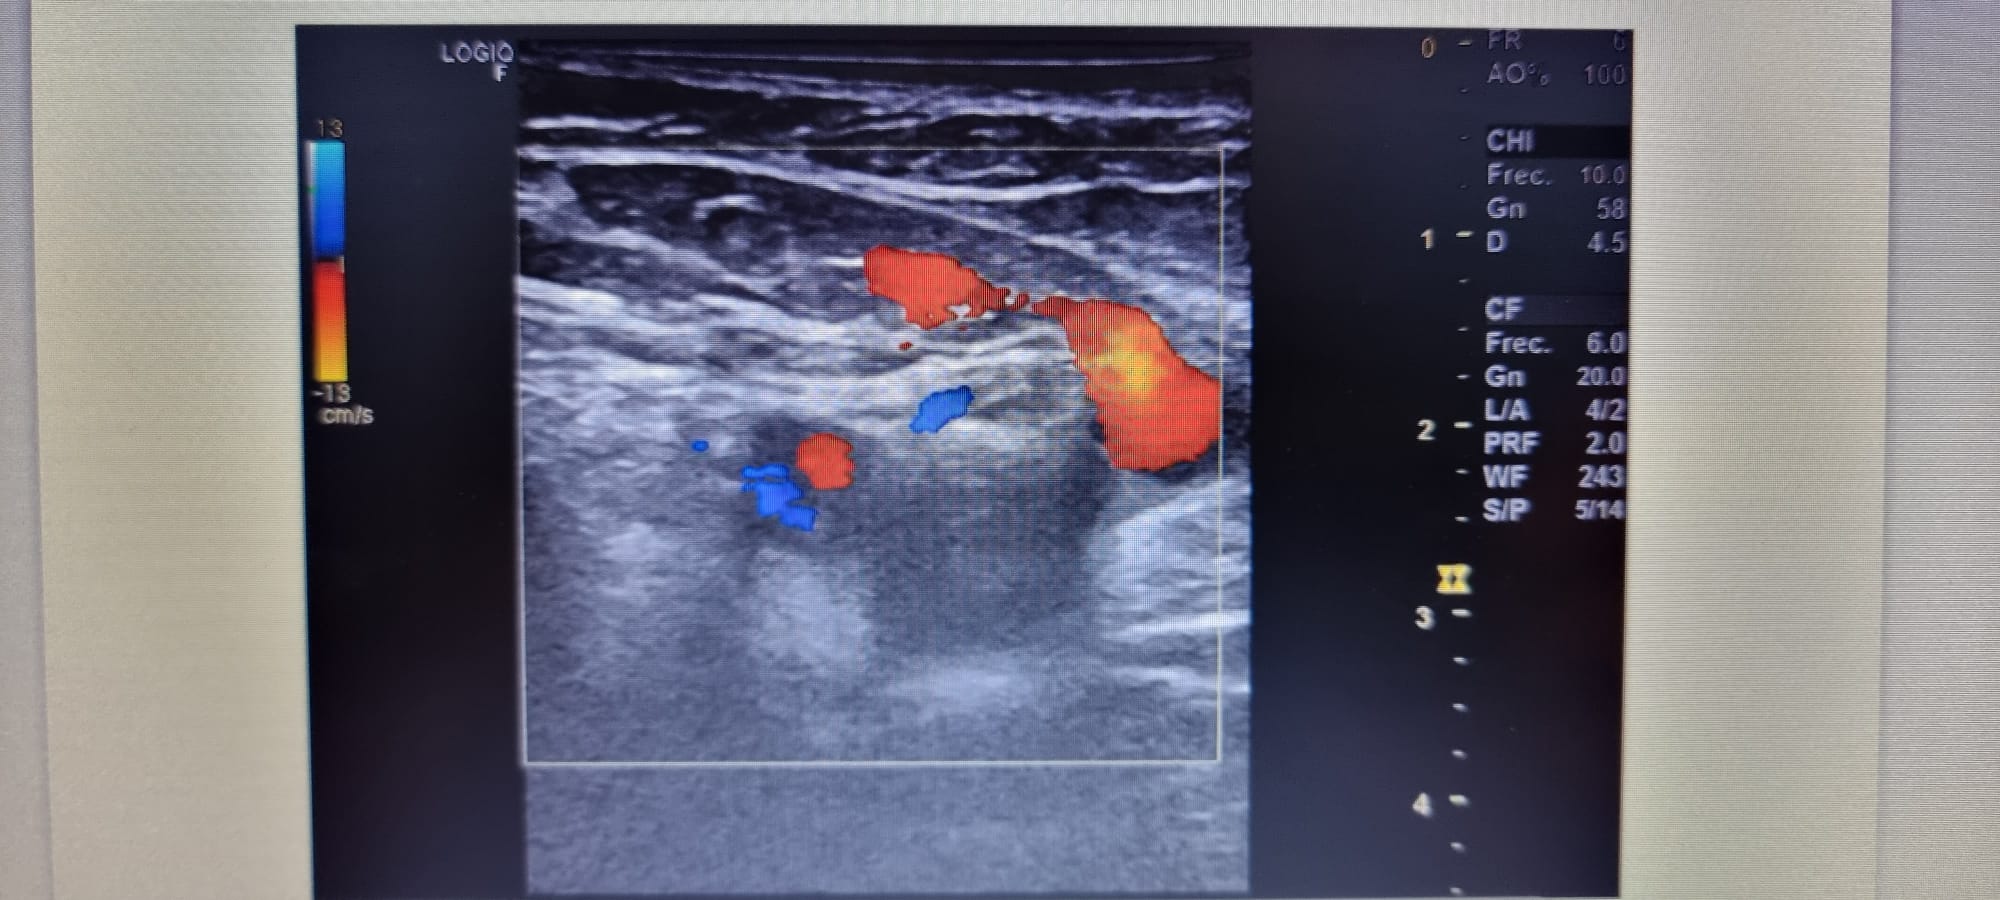

Se realiza ecografia venosa de mid evidenciándose ocupación parcial de femoral común, y segmento de femoral superficial.

Ecografia en Urg hospital: ocupación parcial de la luz de las venas femoral común y segmento proximal de la femoral superficial, ocupación completa de la luz en segmentos medio-distal de la femoral superficial y vena poplitea.